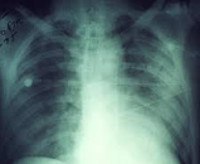

• Рентген грудной клетки. Рентгенологическое исследование определяет очаговые и инфильтрирующие тени, что подтверждает наличие пневмонии. Часто на снимках видны признаки плеврального поражения, возможно, обнаружение экссудата.